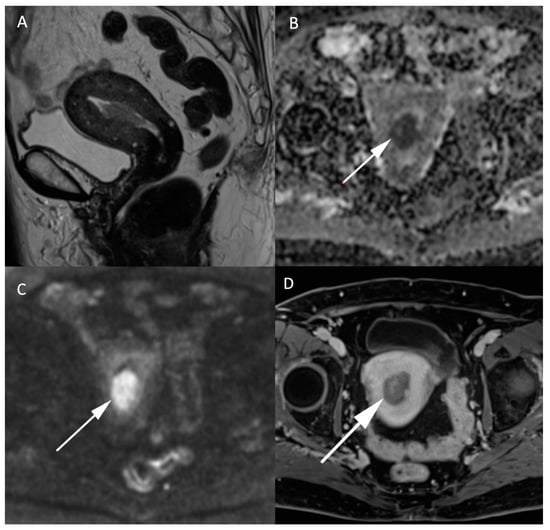

Figure 3.

MR images of an endometrial carcinoma in a 93-year-old woman. (A) Sagittal T2W image in the endometrial cavity with extension in the myometrium smaller than 50% of its thickness. (B) ADC map shows a restricted diffusion in the endometrial carcinoma visible as a “dark” area (arrow) in opposition with (C) high signal (arrow) on high b-value images (b = 1000 s/mm2). (D) post injection of gadolinium T1W image shows the endometrial carcinoma (arrow) with an enhancement less than the myometrium’s muscle.